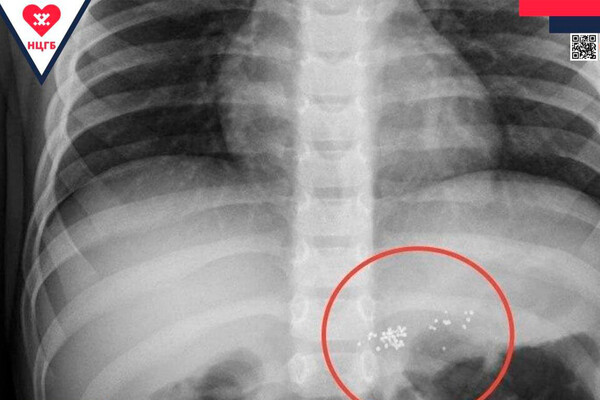

Врачи Новоуренгойской центральной городской больницы осмотрели маленького мальчика, который во время игры раскусил ртутный градусник и проглотил его содержимое. Об этом сообщили в пресс-службе медицинского учреждения.

«Проглоченная ртуть не опасна, токсичны только ее пары. Поэтому ребенка обследовали и оставили на несколько дней под амбулаторным наблюдением», — пояснили в пресс-службе больницы.

Врачи отметили, что ртуть, попавшая в желудок, пройдет по пищеварительному тракту и выйдет с калом. Медики некоторое время наблюдали за пациентом, убедившись, что все хорошо, ребенка отпустили.